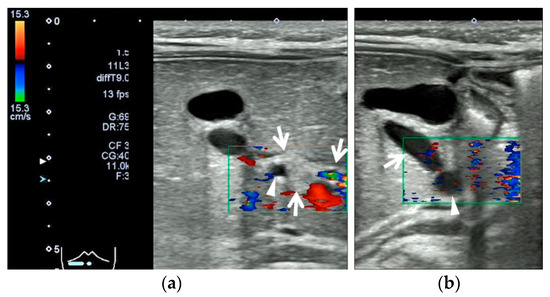

2.2. Case 2: 67-Day-Old Girl